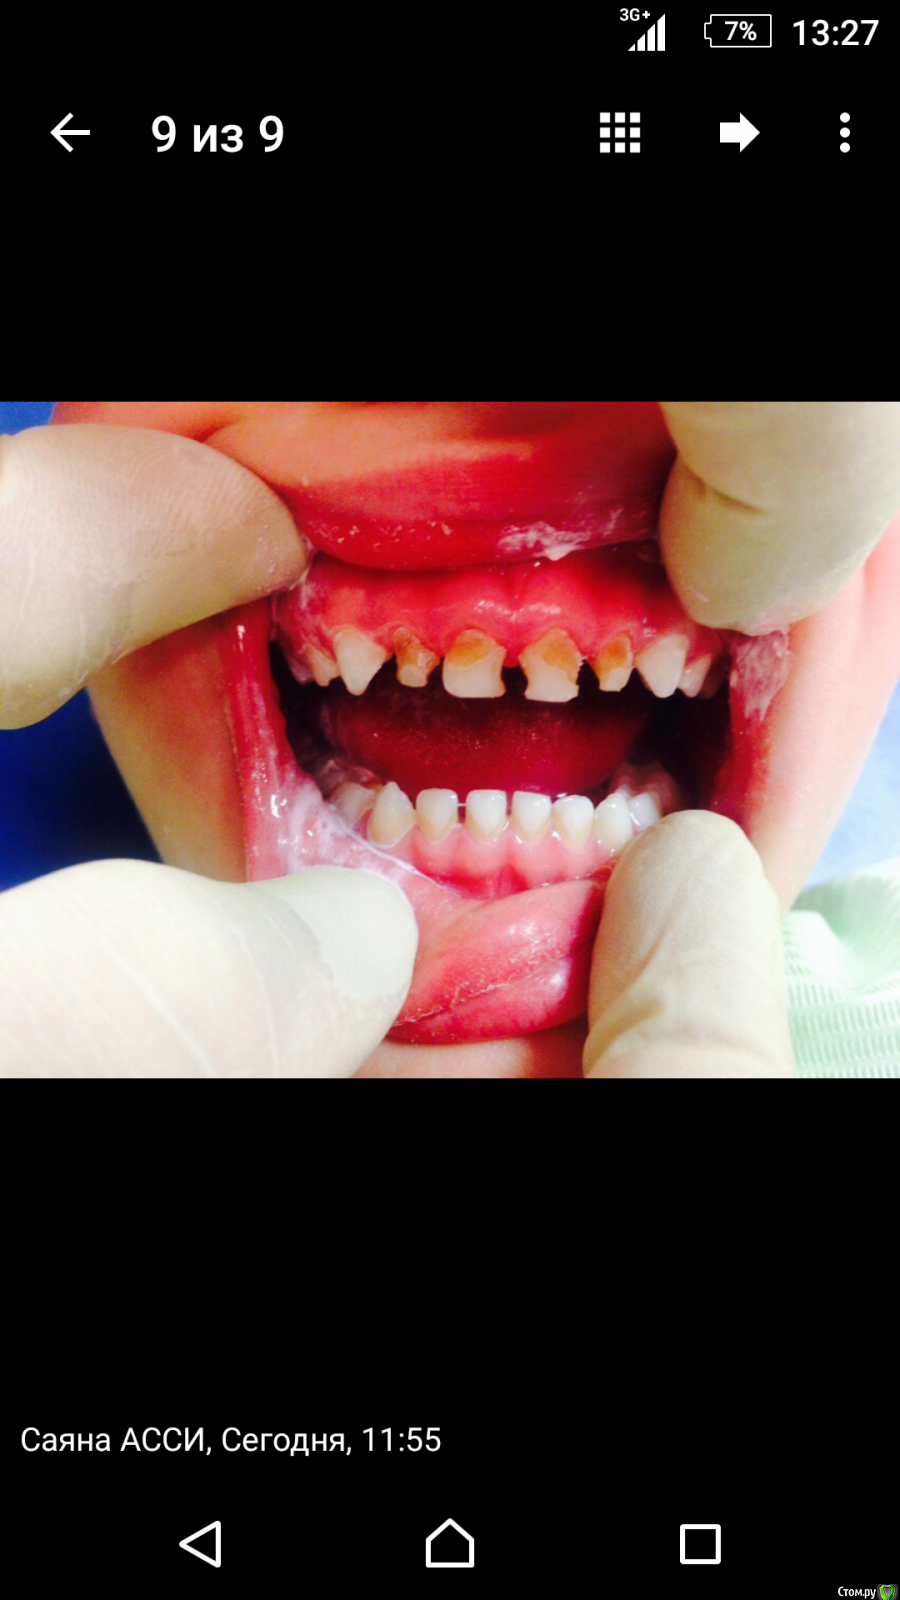

Доктор Саша Опубликовано 12 ноября, 2015 Поделиться Опубликовано 12 ноября, 2015 Ребенку 4,5. Мама просит эстетику. Что делать? Помогите советом. Ссылка на комментарий

CRAZYDUCK Опубликовано 12 ноября, 2015 Поделиться Опубликовано 12 ноября, 2015 (изменено) Ребенку 4,5. Мама просит эстетику. Что делать? Помогите советом.Как ребенок относится к лечению, спокойный, контактный? Если да , то нет проблем .Сначала снимок ,но лечить нужно будет скорее всего с экстирпацией пульпы во всех резцах, пломбирование каналов ЦОЭ или метапекс( но от метапекса чуть пожелтеют).Реставрация дефектов - в идеале коронки ( типа НУ смайл, но это я мечтаю , можно и композитом , только предупредите о возможных сколах при приеме жесткой пищи.( Ктя Геранина описывала в одной теме как изготавливает такие реставрации , укрепляя их стекловолокном), я и просто восстанавливаю, но бывает скалываются.Если дите неконтактное, то тоже самое лечение, толькл с седацией или наркозом. Если опыта лечения еще нет , то лучше каки-нибудь другие зубки полечить сначала, на резцы анестезия все равно чувствуется Изменено 12 ноября, 2015 пользователем CRAZYDUCK 1 Ссылка на комментарий

Джима Опубликовано 13 ноября, 2015 Поделиться Опубликовано 13 ноября, 2015 Доктор Саша, а чего это Вы вдруг совета спрашиваете, вроде ж ничё сложного Согласна, что первый раз в жизни лучше лечить не это, а это - лучше на сладкое оставить. Кстати, в чём дитё вымазано, в пасте? Знакомились - гигиену делали? Здесь можно бы непрямым путём, снять частичный оттиск прям с того, что есть, подготовить композитные колпачки из того же эстелайта, чтоб не мучиться на месте с контактами и моделировкой, а в следующее посещение пусть мама смотивирует, чтоб ребёнок шёл "за красивыми белыми зубками" - заморозить всё наглухо (это ж один раз! самый последний, можно инфильтрацию начинать сканданестом от 54 и потихоньку "подползти" артикаином к фронту, если дитё очень нежное), эндо, где надо, нить ретракционную, и на жидкотекучий колпачки. Думаю, управитесь за полтора часа со всеми заморозками и полировками с перерывами на поговорить, отдохнуть, рассмотреть и т.п. 1 Ссылка на комментарий

Доктор Саша Опубликовано 14 ноября, 2015 Поделиться Опубликовано 14 ноября, 2015 Доктор Саша, а чего это Вы вдруг совета спрашиваете, вроде ж ничё сложного Согласна, что первый раз в жизни лучше лечить не это, а это - лучше на сладкое оставить. Кстати, в чём дитё вымазано, в пасте? Знакомились - гигиену делали? Здесь можно бы непрямым путём, снять частичный оттиск прям с того, что есть, подготовить композитные колпачки из того же эстелайта, чтоб не мучиться на месте с контактами и моделировкой, а в следующее посещение пусть мама смотивирует, чтоб ребёнок шёл "за красивыми белыми зубками" - заморозить всё наглухо (это ж один раз! самый последний, можно инфильтрацию начинать сканданестом от 54 и потихоньку "подползти" артикаином к фронту, если дитё очень нежное), эндо, где надо, нить ретракционную, и на жидкотекучий колпачки. Думаю, управитесь за полтора часа со всеми заморозками и полировками с перерывами на поговорить, отдохнуть, рассмотреть и т.п. Паста полировочная сделал последний моляр... Отвалится непрямой метод. Коронка у нас стоит нью смайл 7 килорублей. Мама не соглашается... Эндо надо полюбому делать Ссылка на комментарий

Доктор Саша Опубликовано 14 ноября, 2015 Поделиться Опубликовано 14 ноября, 2015 то есть ребёнок уже с опытом лечения. Спокойно сидит? а почему отвалится-то?..Потому что ребя активный чел... Не сидит на месте. Может что-то другое есть? Ссылка на комментарий

Джима Опубликовано 14 ноября, 2015 Поделиться Опубликовано 14 ноября, 2015 Потому что ребя активный чел... Не сидит на месте. Может что-то другое есть?так в том и смысл, чтоб быстро сделать длинную работу активному ребёнку. в первое посещение оттиск, перед этим, если всё будет эндо, режущие края стесать и боковые стенки, там, где эмаль целая. Чтоб восстанавливать потом не на всю высоту. Если глубоко резцы смыкаются, тогда ещё окклюзионные точки по копирке стесать.Потом в спокойном одиночестве сделали модельку из супергипса, сделали тоненькие невысокие свободные короночки из композита. В руках и делать быстрее и легче, и усадка под контролем.Потом во рту анестезия, препарирование всего плохого + всего, что может мешать сажать работу, эндодоступ вестибулярно, по очереди все депульпировали-промыли-эндовак-метапекс-ионосит, потом нити, помыли-посушили и меряем коронки. Если и придётся что-то подгонять, то совсем граммульку, а скорее всего и не придётся. Если прям ну очень активный и неуёмный, можно зеркало дать в руки, чтоб смотрел и контролировал, а взамен взять клятву молчать и замереть. Коффер я бы тут, честно говоря, не ставила. Протравка-бонд-потушили свет-все четыре на жидкотекучий надели-лишнее зондом убрали-всё отсветили со всех сторон-полировка-сняли нити-полировка. Благодаря тому, что одной порцией с конденсацией под колпачком вносится жидкий, усадка будет минимальной и как бы обжимающей, слоёв, считай, всего два (жидкий+коронка), так что ничего не сколется, если не будет гвозди грызть. А если и подколется чуть-чуть со временем, отремонтировать легко. И если уж совсем так уж думать, то прямая реставрация сколется тогда ещё быстрее, да и НьюСмайл отвалится с тем же успехом А нового-другого я ничего не знаю 2 Ссылка на комментарий